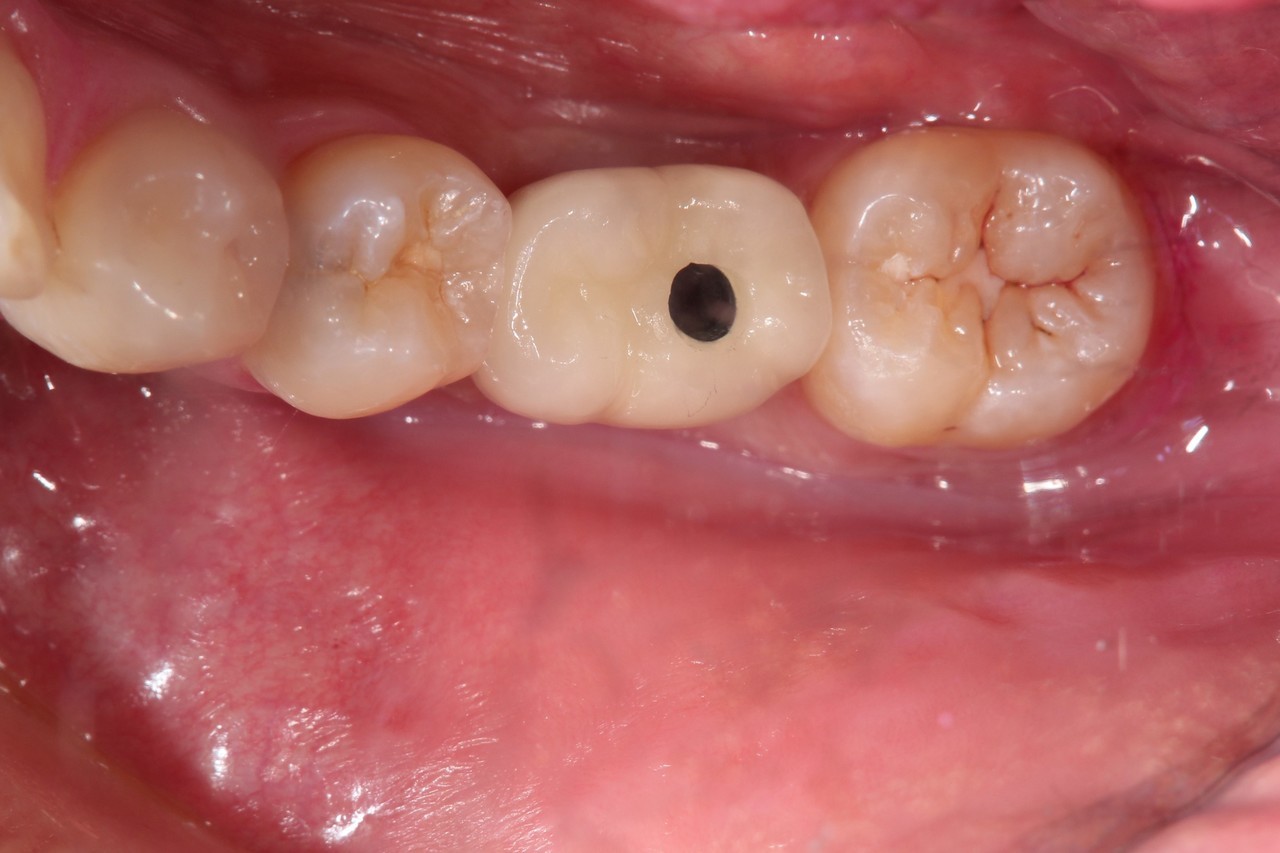

奥歯インプラント(スクリュー固定)

(伊東市 女性)

治療の流れ

むし歯で歯を失ってしまいました。

インプラントを埋入し、最終的な被せ物を装着しました。(ネジ穴をふさぐ前)

ネジ穴をふさぐとこの様な状態になります。